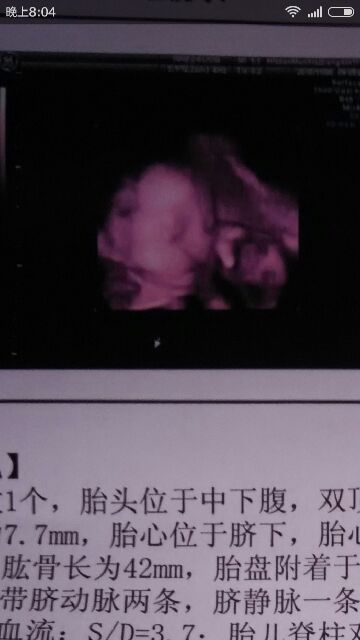

目前想起这么多,宝妈有疑问的可以回复问我,下面是我两个月,四个月,还有六个月的B超单!